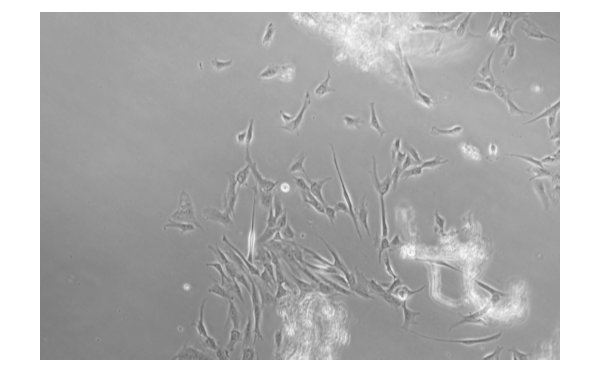

外周血中的NK细胞是最常见的来源之一。分离外周血NK细胞的方法包括密度梯度离心、免疫磁珠分选、细胞贴壁法等。离心分离是最常用的方法之一,通过梯度离心可以分离出富含NK细胞的单个细胞层。接着可以使用NK细胞激活和扩增培养基对NK细胞进行培养和激活,以增强其细胞毒性和免疫反应性。

脐带血作为胎儿与母体之间的交通通道,在其中富含干细胞和NK细胞等免疫细胞。分离脐带血NK细胞的方法和外周血类似,但由于脐带血中NK细胞浓度较低,需要更多的前处理步骤来提高NK细胞的纯度。在培养过程中,添加适当的生长因子和细胞因子能够促进NK细胞的增殖和杀伤活性。

除了血液来源外,NK细胞还可以来自淋巴组织、脾脏、骨髓等器官。分离组织中的NK细胞需要更多的手术操作和前处理步骤,但这些NK细胞在体内可能具有更强的免疫杀伤作用。在培养过程中,需要根据不同来源的组织类型优化培养条件,例如添加不同种类的生长因子和细胞激活剂等。

通过诱导多能干细胞(iPSC)向NK细胞分化的方法也逐渐成熟。通过向iPSC中诱导表达NK细胞特定标志物并加入特定生长因子,可以使iPSC分化为NK细胞。这种来源的NK细胞可以大规模生产,并且在临床治疗中具有广阔的应用前景。